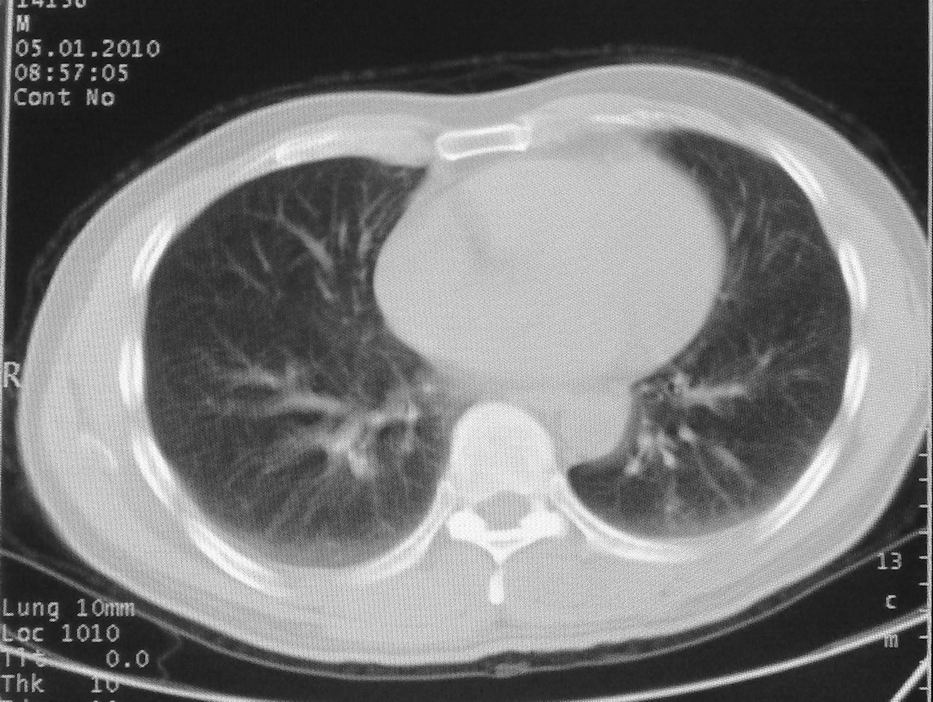

男,51岁,左胸前区不适数天。

薄壁空洞,边缘毛刺,胸膜凹陷,考虑肺癌,结核不排除。

考虑左肺下叶感染性病变。

考虑左肺下叶感染性病变。支持!建议查痰、hrct。

考虑左肺下叶感染性病变,不除外肺栓。